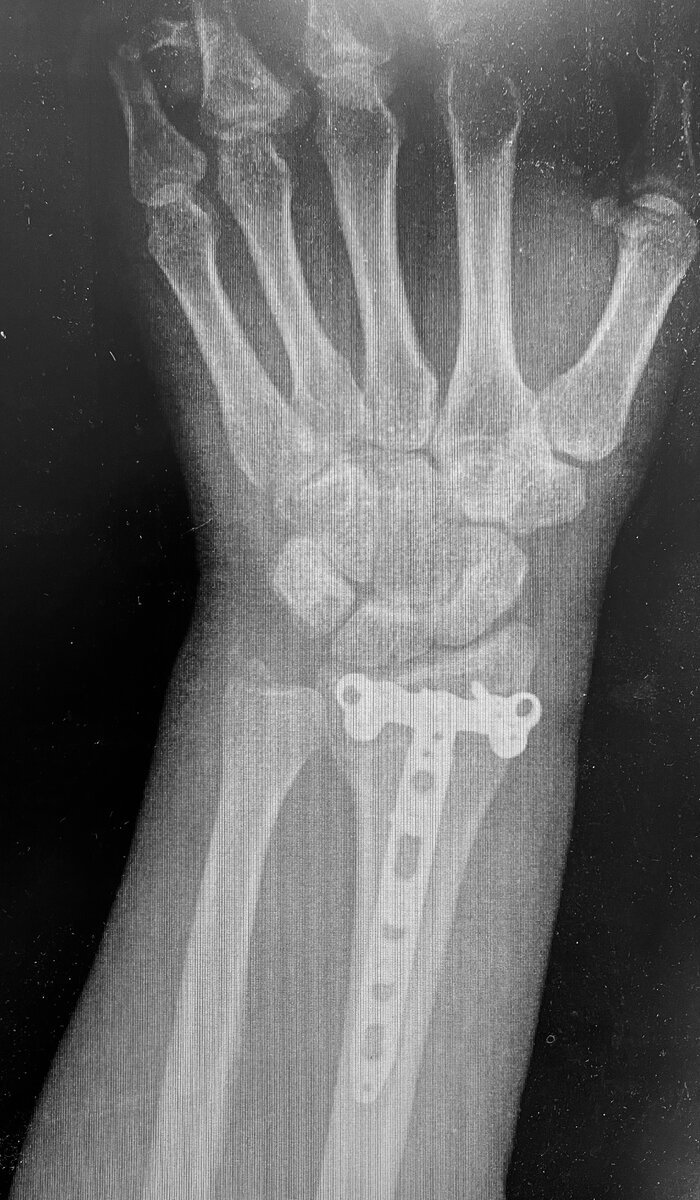

На R-гр. в прямой проекции состояние после металлостеосинтеза, стояние отломков удовлетворительное

R-гр боковой проекции лучезапястного сустава